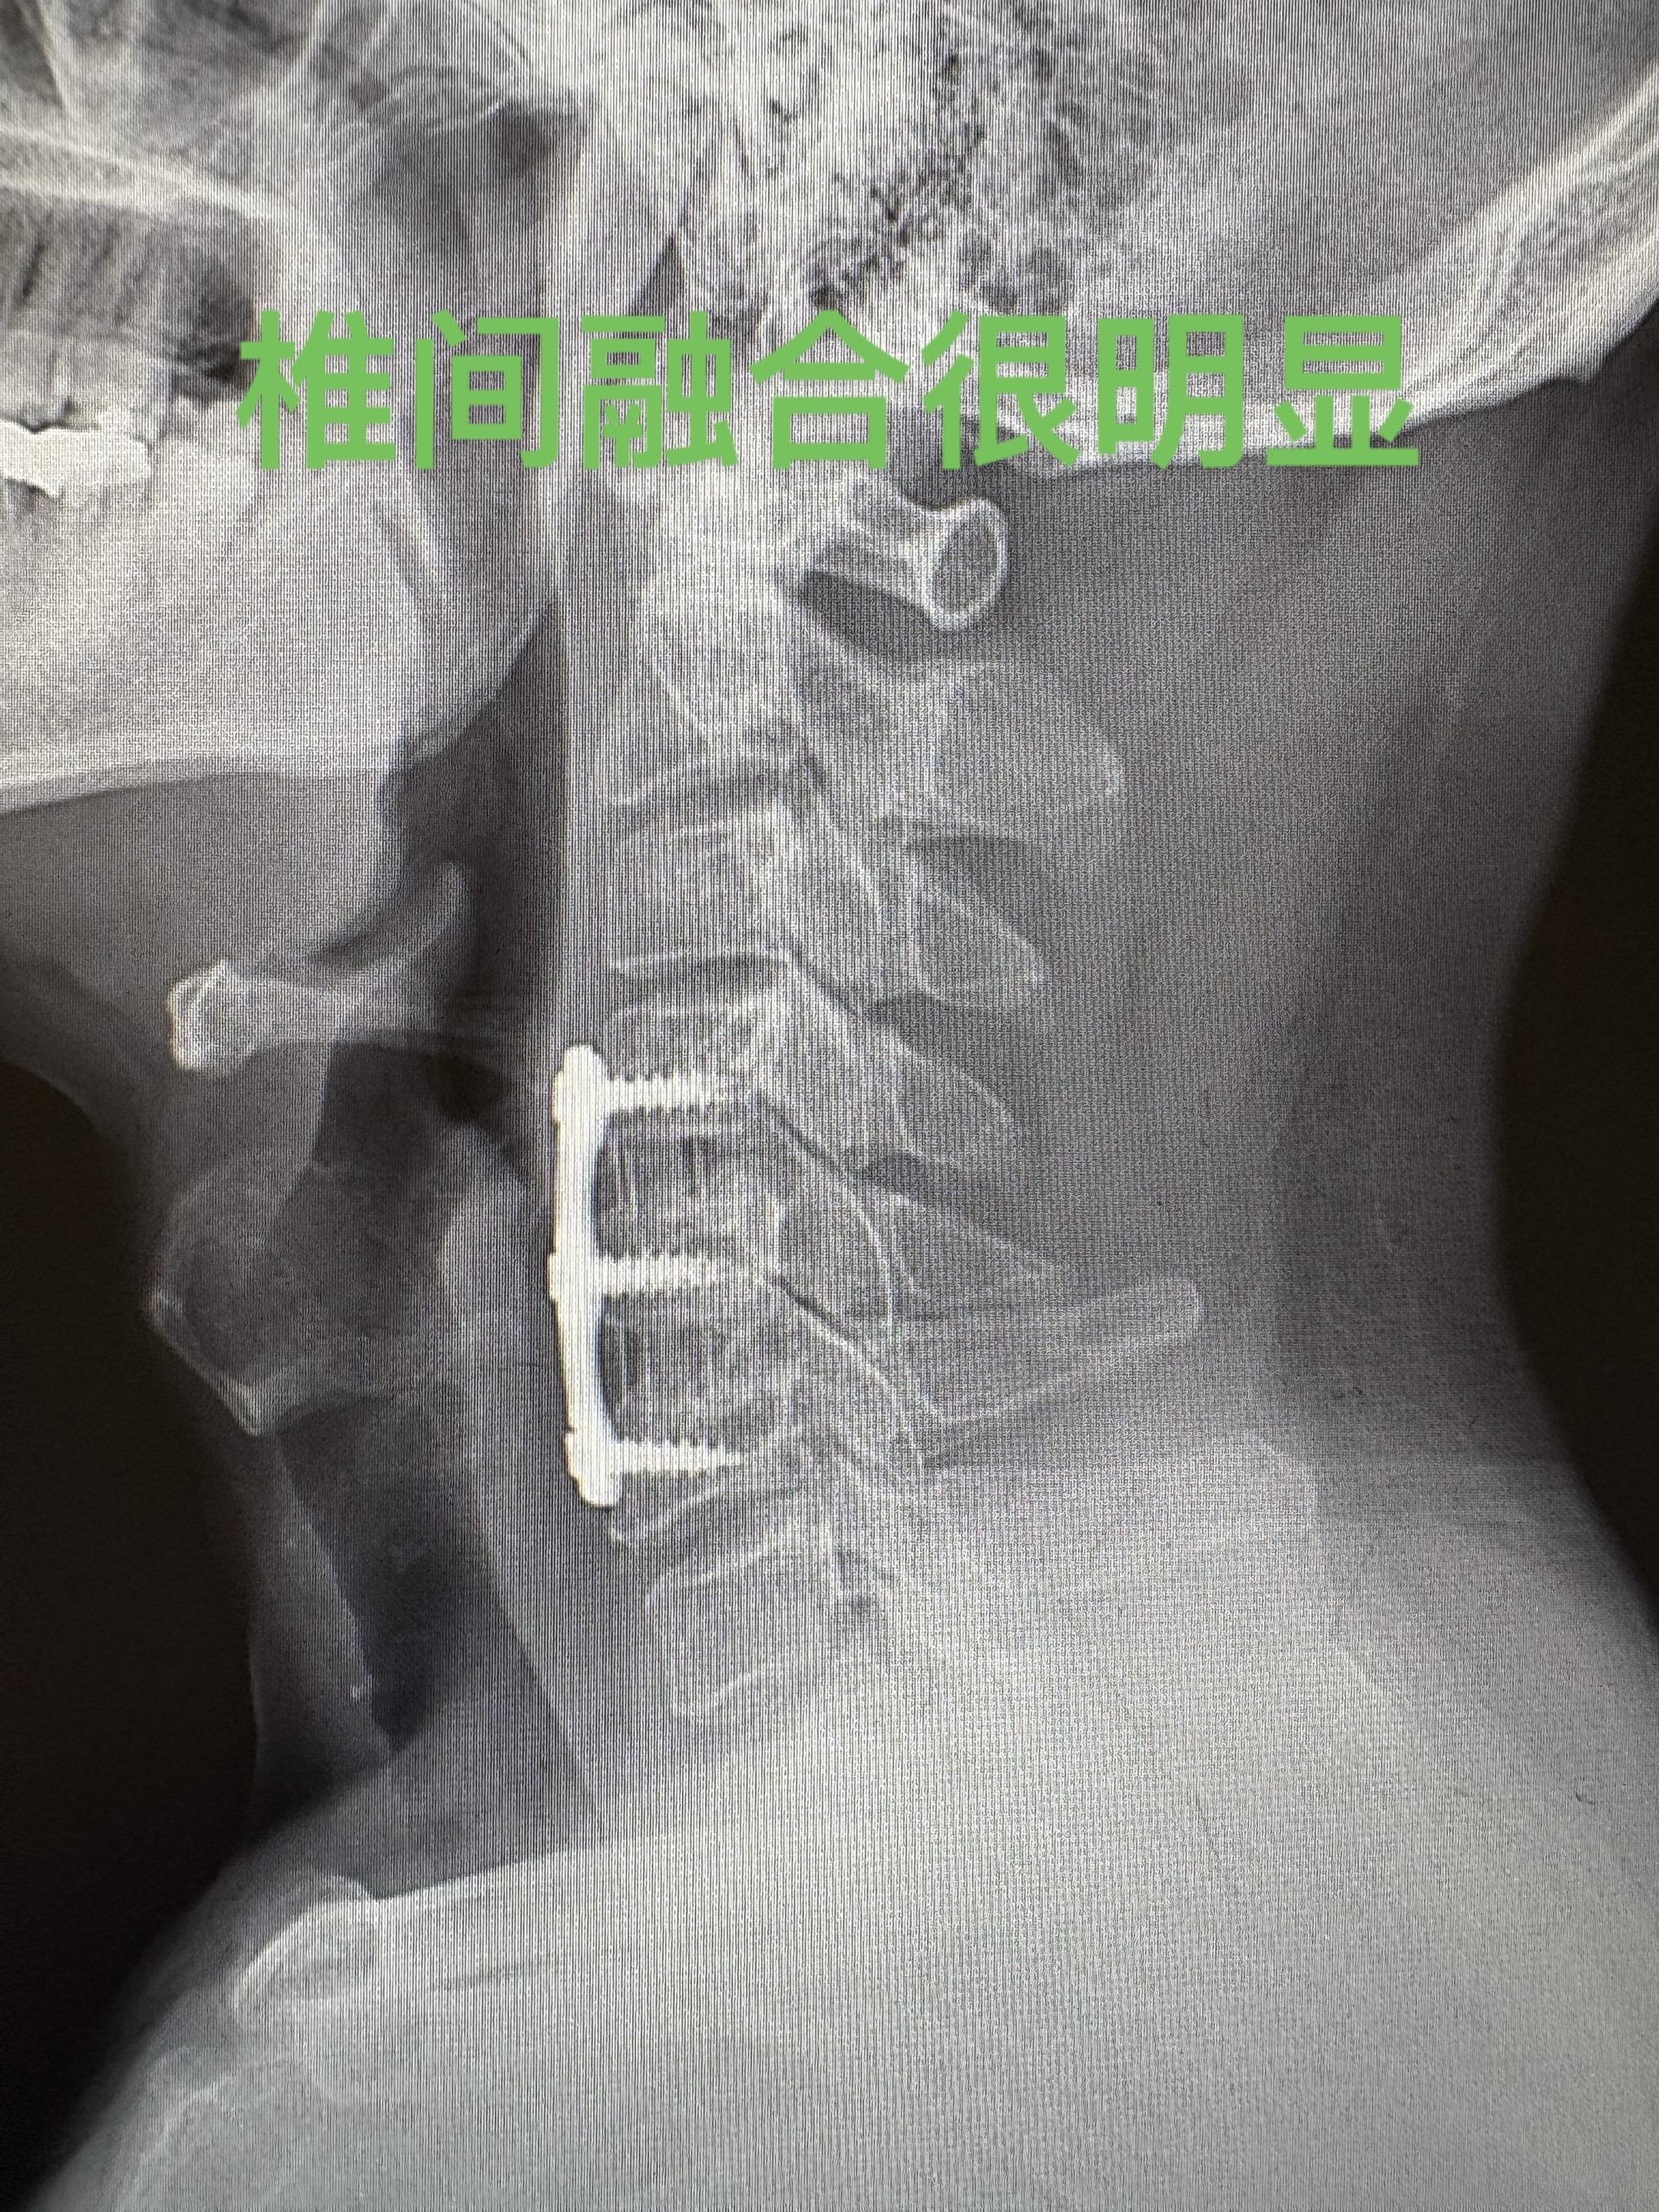

颈椎病手术后后一年复查。手术做完一年,患者手术前的踩棉花感已经消失,但有时候会有一侧肢体的无力感。手术很顺利,术后复查的磁共振以及X光片也很满意。病人唯一的遗憾就是没有及时发现,当时当腰椎间盘突出治疗浪费了不少时间。劝慰患者放松心态,一般此种症状两年之内还是会不断地改善。